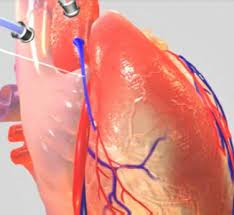

Congenital Heart Surgeries

Congenital Heart Surgeries (CHDs) are structural defects of the heart that a child is born with. These disorders influence blood circulation in the heart and can be as basic as a small hole in the heart.